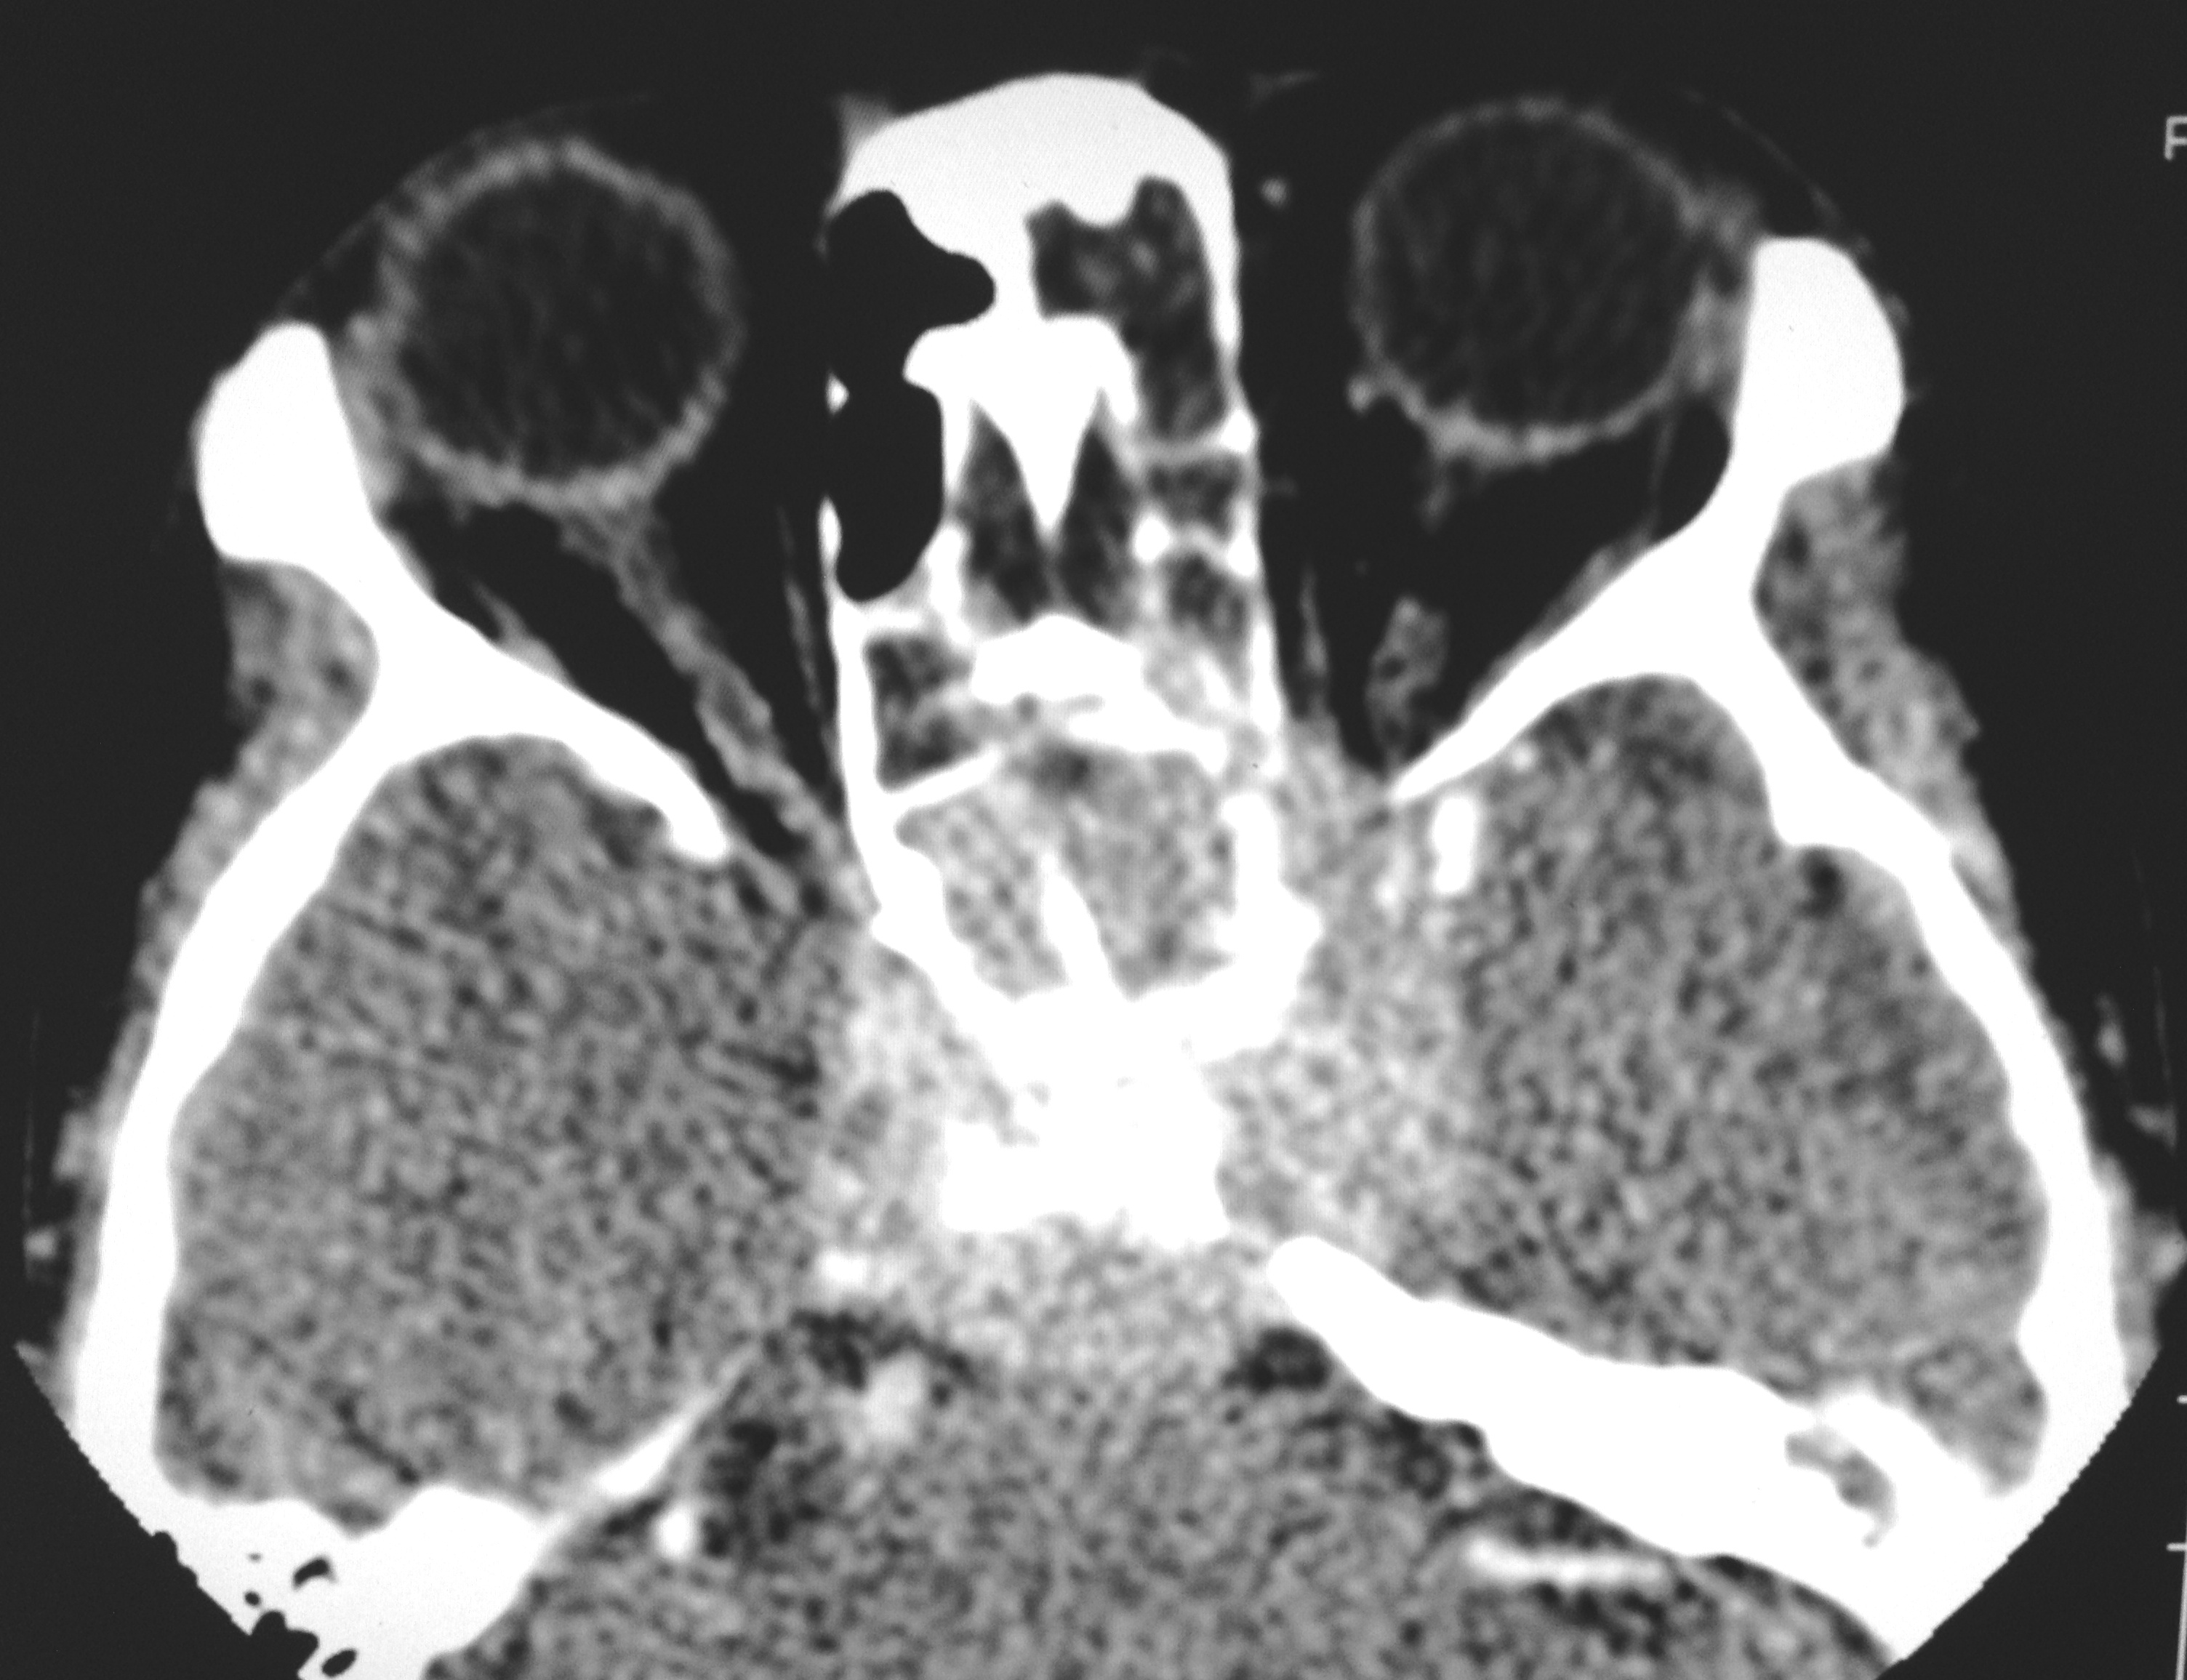

Nasopharyngeal carcinoma is a malignant disease and is more common in males than in females with M:F ratio of 3:1. It has a bimodal peak at 16-20 and 46-50 years of age. Orbital involvement is seen in 3.2% and bilateral orbital invasion occurs in 0.7% of patients with nasopharyngeal carcinoma. Imaging has significant role in detecting the early nasopharyngeal carcinoma, tumor staging, involvement of lymph node, monitoring the patients after the therapy, to detect recurrence and radiation associated changes in the soft tissue and bone. We report a case of aggressive nasopharyngeal carcinoma in 22 years old male who presented with rapidly progressive diminution of vision.